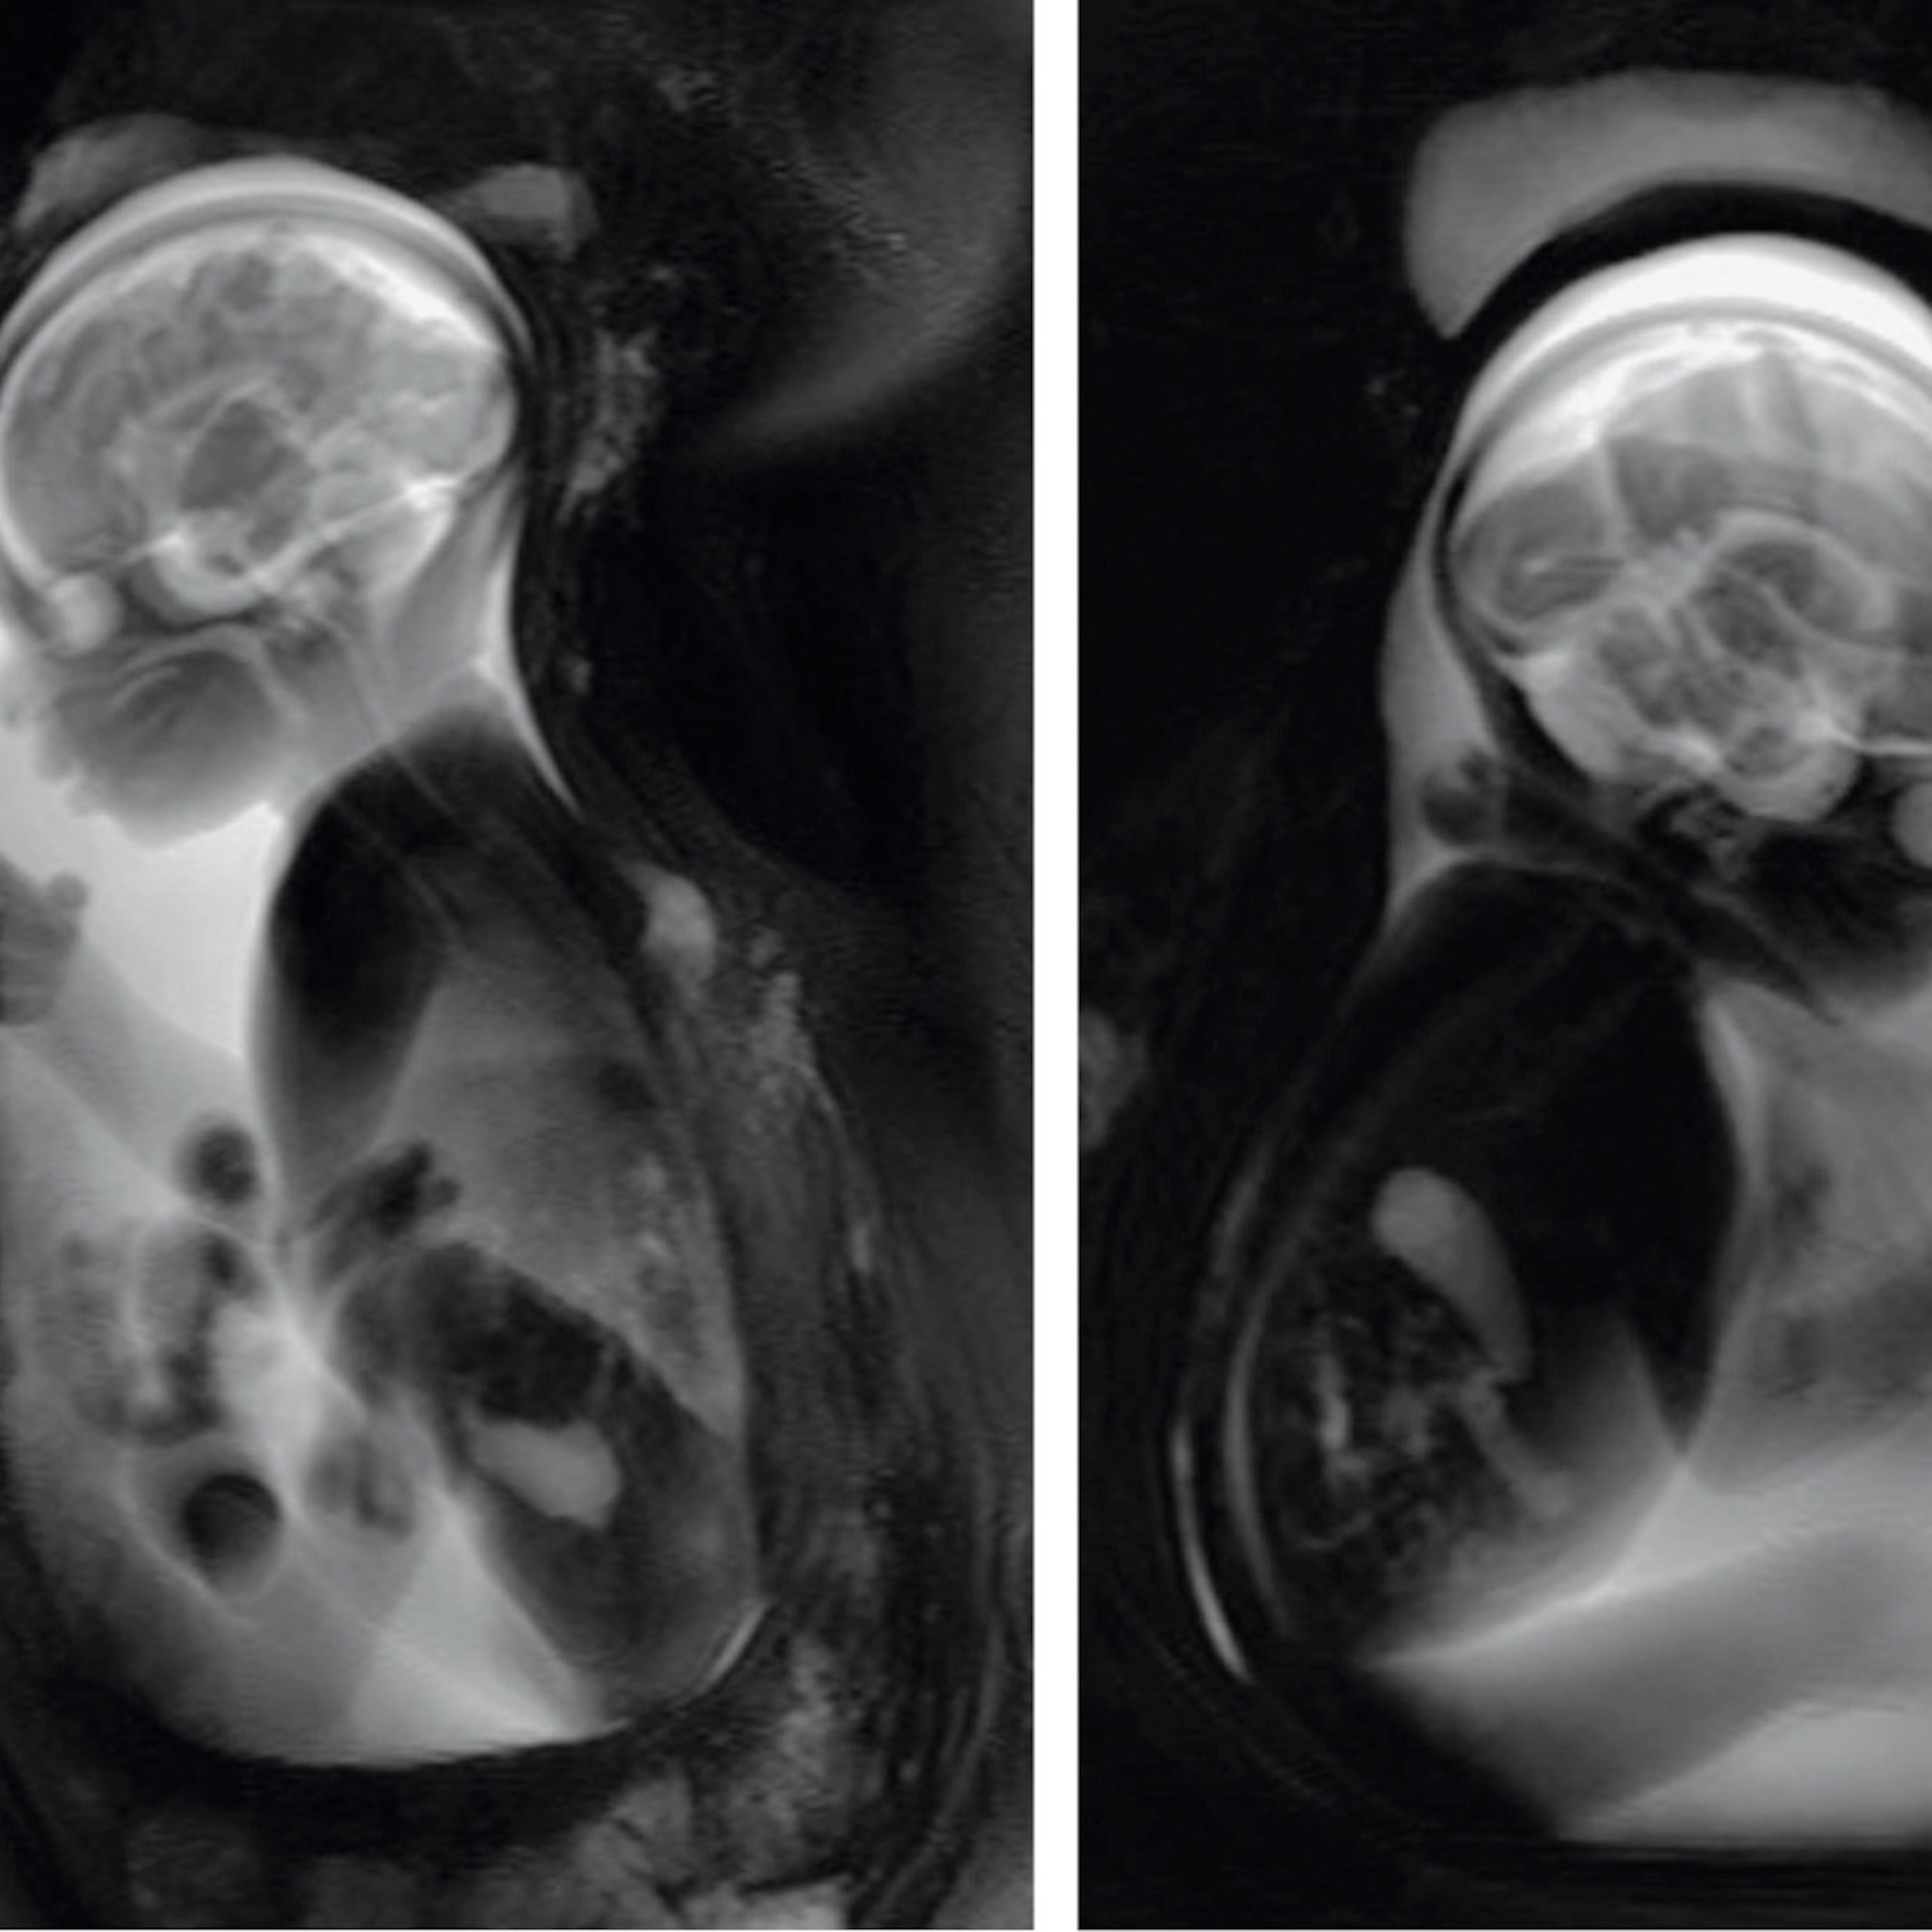

The 39-year-old convicted murderer died from lethal injection at 12:31 a.m. on August 5, 1993. Spitzer flew to Texas to collect the body, which was frozen, sectioned into nearly 2,000 millimeter-thick slices, and digitized. The images are on the National Library of Medicine’s website, where anyone can file an application for the data.

The female, a 59-year-old from Maryland who had died of heart disease, was sectioned a year later. Spitzer’s group, having proved the technique to the National Library of Medicine, cut her into more than 5,000 slices only 0.33 millimeter thick. As of this writing, 4,000-plus licenses for the Visible Human data have been issued for applications ranging from building better hip joints to creating virtual crash dummies.

One day in a lecture hall on campus, I watched Spitzer demonstrate a dissecting program he’d devised using the data. With the sweep of a mouse, he stripped the musculature to reveal the skeleton, then showed a cross section of an upper thigh that looked like nothing so much as a raw haunch of meat. He isolated the circulatory system, hovered over the heart, visualized it from a different angle, and reassembled the cadaver in its entirety.

Cutting the NIH-funded Visible Human Male into roughly 2,000 slices took Spitzer four months in 1993. Twenty-four years later, Susan Potter was cut into 27,000 slices in 60 days. Next comes the painstaking, time-consuming process of outlining the structures—tissue, organs, vessels—on each digital slice to highlight the skeleton, nerves, and vasculature in exquisite detail. That will take two or three years.

Now when Spitzer looks at Potter on the screen in digitized slices, he says, he sees her pain: the tortured, twisted arteries, the steel screws that stabilized her fractured cervical spine, an oddly misshapen kidney, and the arthritic joints that map the relentless decline into old age.